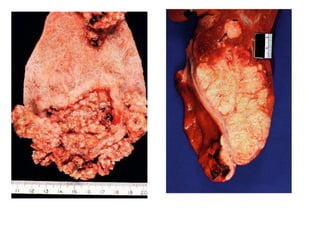

Morfología Infiltrantes Exofíticos Adenocarcinomas Invasión local del hígado, conducto quístico y ganglios linfáticos.

Morfología Infiltrantes ExofíticosAdenocarcinomas Invasión local del hígado, conducto quístico y ganglios linfáticos.